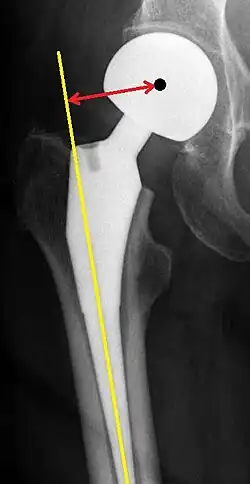

Post-operative projectional radiography is routinely performed to ensure proper configuration of hip prostheses.

The direction of the acetabular cup influences the range of motion of the leg, and also affects the risk of dislocation.[16] For this purpose, the acetabular inclination and the acetabular anteversion are measurements of cup angulation in the coronal plane and the sagittal plane, respectively.

![Leg length discrepancy after hip replacement is calculated as the vertical distance between the middle of the minor trochanters, using the acetabular tear drops[95] or the transischial line[16] as references for the horizontal plane. A discrepancy of up to 1 cm is generally tolerated.[95][16]](./_assets_/Leg_length_discrepancy_after_hip_replacement.jpg)